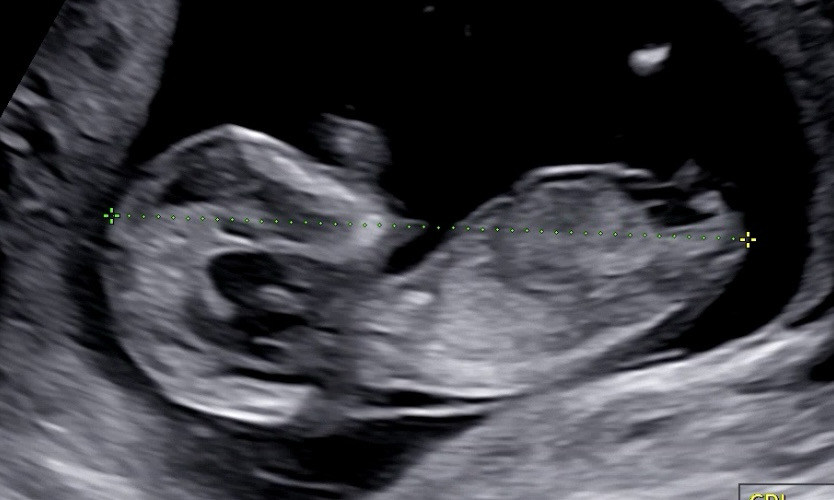

12주차인데 다들 봐주세요~!

여자아이일까 남자아이일까 계속 보게 되요..! 혹시 다들 어떻게 생각하실까요?!